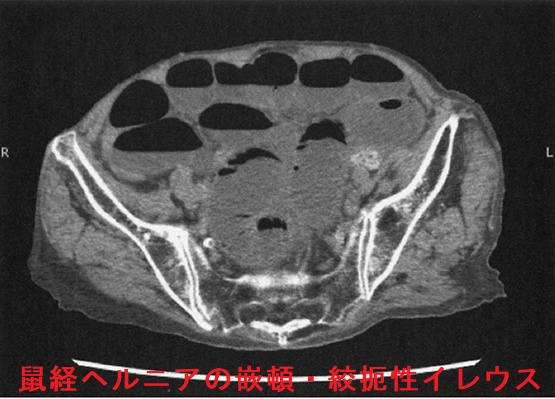

外鼠径ヘルニア(間接鼠径ヘルニア)では、腸管が内鼠径輪→鼠径管を経て外鼠径輪に脱出。陰嚢腫大は外鼠径ヘルニア特有の症状です。内鼠径ヘルニアに比べてヘルニア門が狭く嵌頓(かんとん)しやすい。

CT画像でヘルニア門が下腹壁動脈の外側なら外鼠径ヘルニア、内側なら内鼠径ヘルニアです。